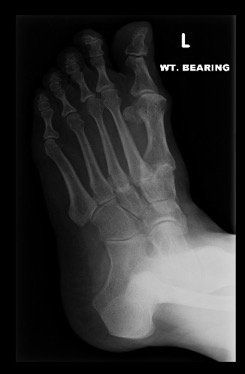

Midfoot arthritis refers to arthritis in the middle part of the foot. There are a number of joints that make up this part of the foot and arthritis in this area presents with degenerative changes. Degenerative changes are depicted by pain in the area, instability of the joint, narrowing of the joint space, osteophytes or bone spurs, cystic areas within the bone, damage to the joint cartilage, and laying down of extra bone.

Surgery for midfoot arthritis ranges from simple to more complex procedures. Surgery may involve a “clean-up” of the joint by removing damaged cartilage and bone spurs, resection of a part of the joint, fusion (stiffening) of one or more joints. Medical imaging, such as x-rays and MRIs are usually obtained prior to surgery to determine the extent of the injury and to plan for the proposed surgery.